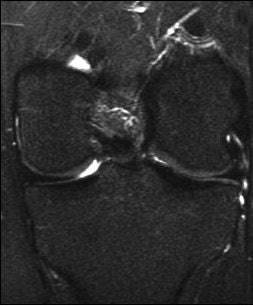

| A 31-year-old man with fast resolution of bone bruise, reticular lesion type. Coronal T2-weighted fast-suppressed images (TR/TE, 12/3,700; fat saturation; section thickness, 3 mm; field-of-view, 180 x 135 mm; matrix, 385 x 224) show fast resolution of bone bruise from baseline (above), to three-week follow-up (middle), and at nine-week follow-up (below). |